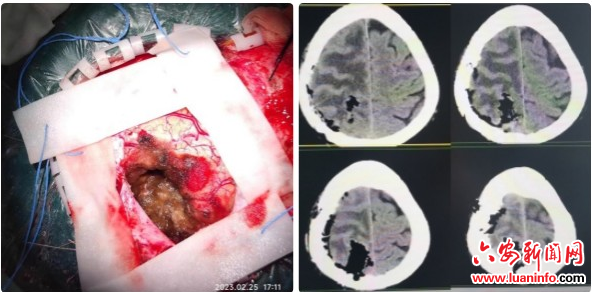

(肿瘤位于脑功能区,压迫回流静脉引起大面积脑水肿)

手术正式开始,在机器人“助手”的导航下,李继波根据术前头颅CT、头颅MRI的数据分析结果,选择最佳开颅范围,精准定位肿瘤范围,成功完整切除肿瘤。

(术中肿瘤全切,术后CT瘤腔内无出血)